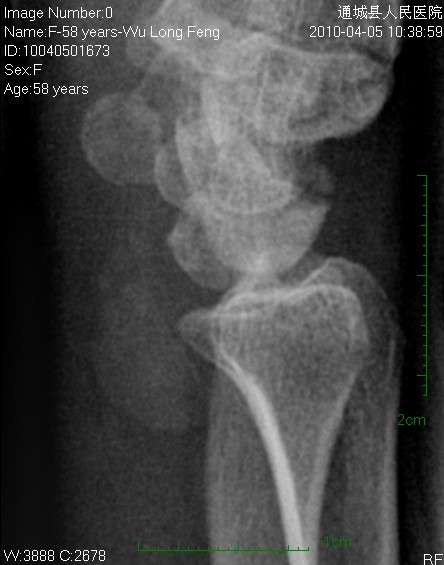

后三张是透视转动下点片放大。

平片见桡前软组织内一密度增高、边缘光整块影

片含诸构成骨无明显骨质破坏,软组织稍肿胀。片示软组织内异常密度影个人考虑为纤维组织增生,伴局部皮肤呈癣样变。考虑:银屑病性关节炎。建议作进一步检查。

这个位置这么大的东西竟然摸不到块,应该不是软组织内的吧。